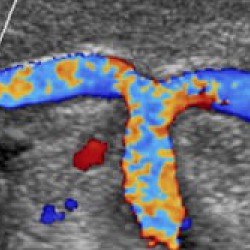

Цветовой допплер:

Да

• Цветной допплер (CD) - Да

• Опция получения трехмерного изображения в режиме цветового допплеровского картирования (трехмерная реконструкция ЦДК) - Да

• Опция получения трехмерного изображения в режиме цветового допплеровского картирования - Да